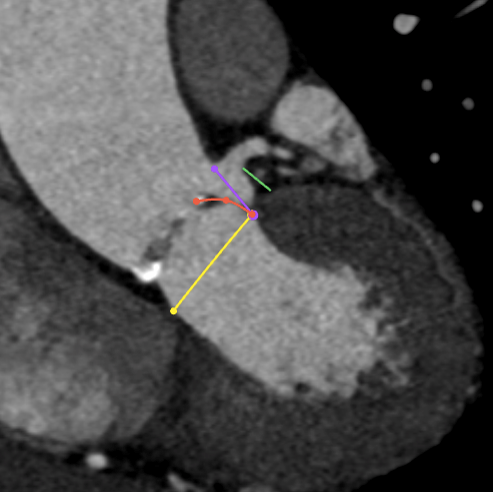

LCA

下缘高度 7.1mm

上缘高度 11.9mm

瓣叶长度 11.8mm

● 冠脉开口高度低,结合窦部高度和宽度、STJ大小、瓣叶长度等,冠脉闭塞风险高,根据预扩张结果决定是否行冠脉保护。